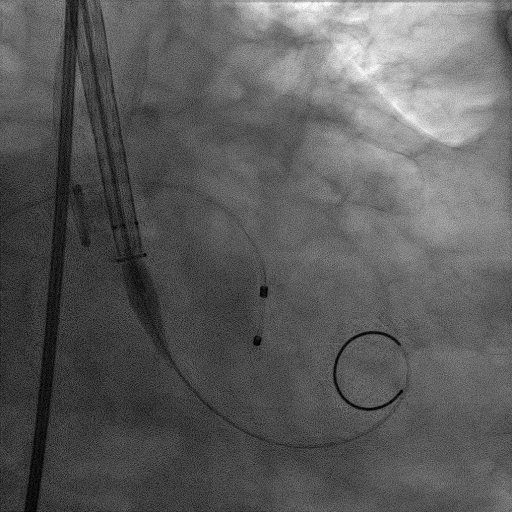

CT提示为该患者三叶瓣,右无轻度融合,冠脉开口高度尚可,窦部空间可,髂总动脉近环形钙化,内径可,计划予以23mm球囊扩张,植入Venus A 26瓣膜。

CAG:LAD近中段弥漫钙化,近段80%狭窄,中段90%狭窄,D190%狭窄,中间支近段90%狭窄,右冠近中段弥漫病变,最重狭窄50%。考虑患者胸痛症状可能为冠心病+AS共同作用,以及患者冠脉病变钙化严重,予以旋磨+PCI+TAVR一站式处理。

造影提示微少量返流,压力监测提示主动脉瓣压差7mmHg